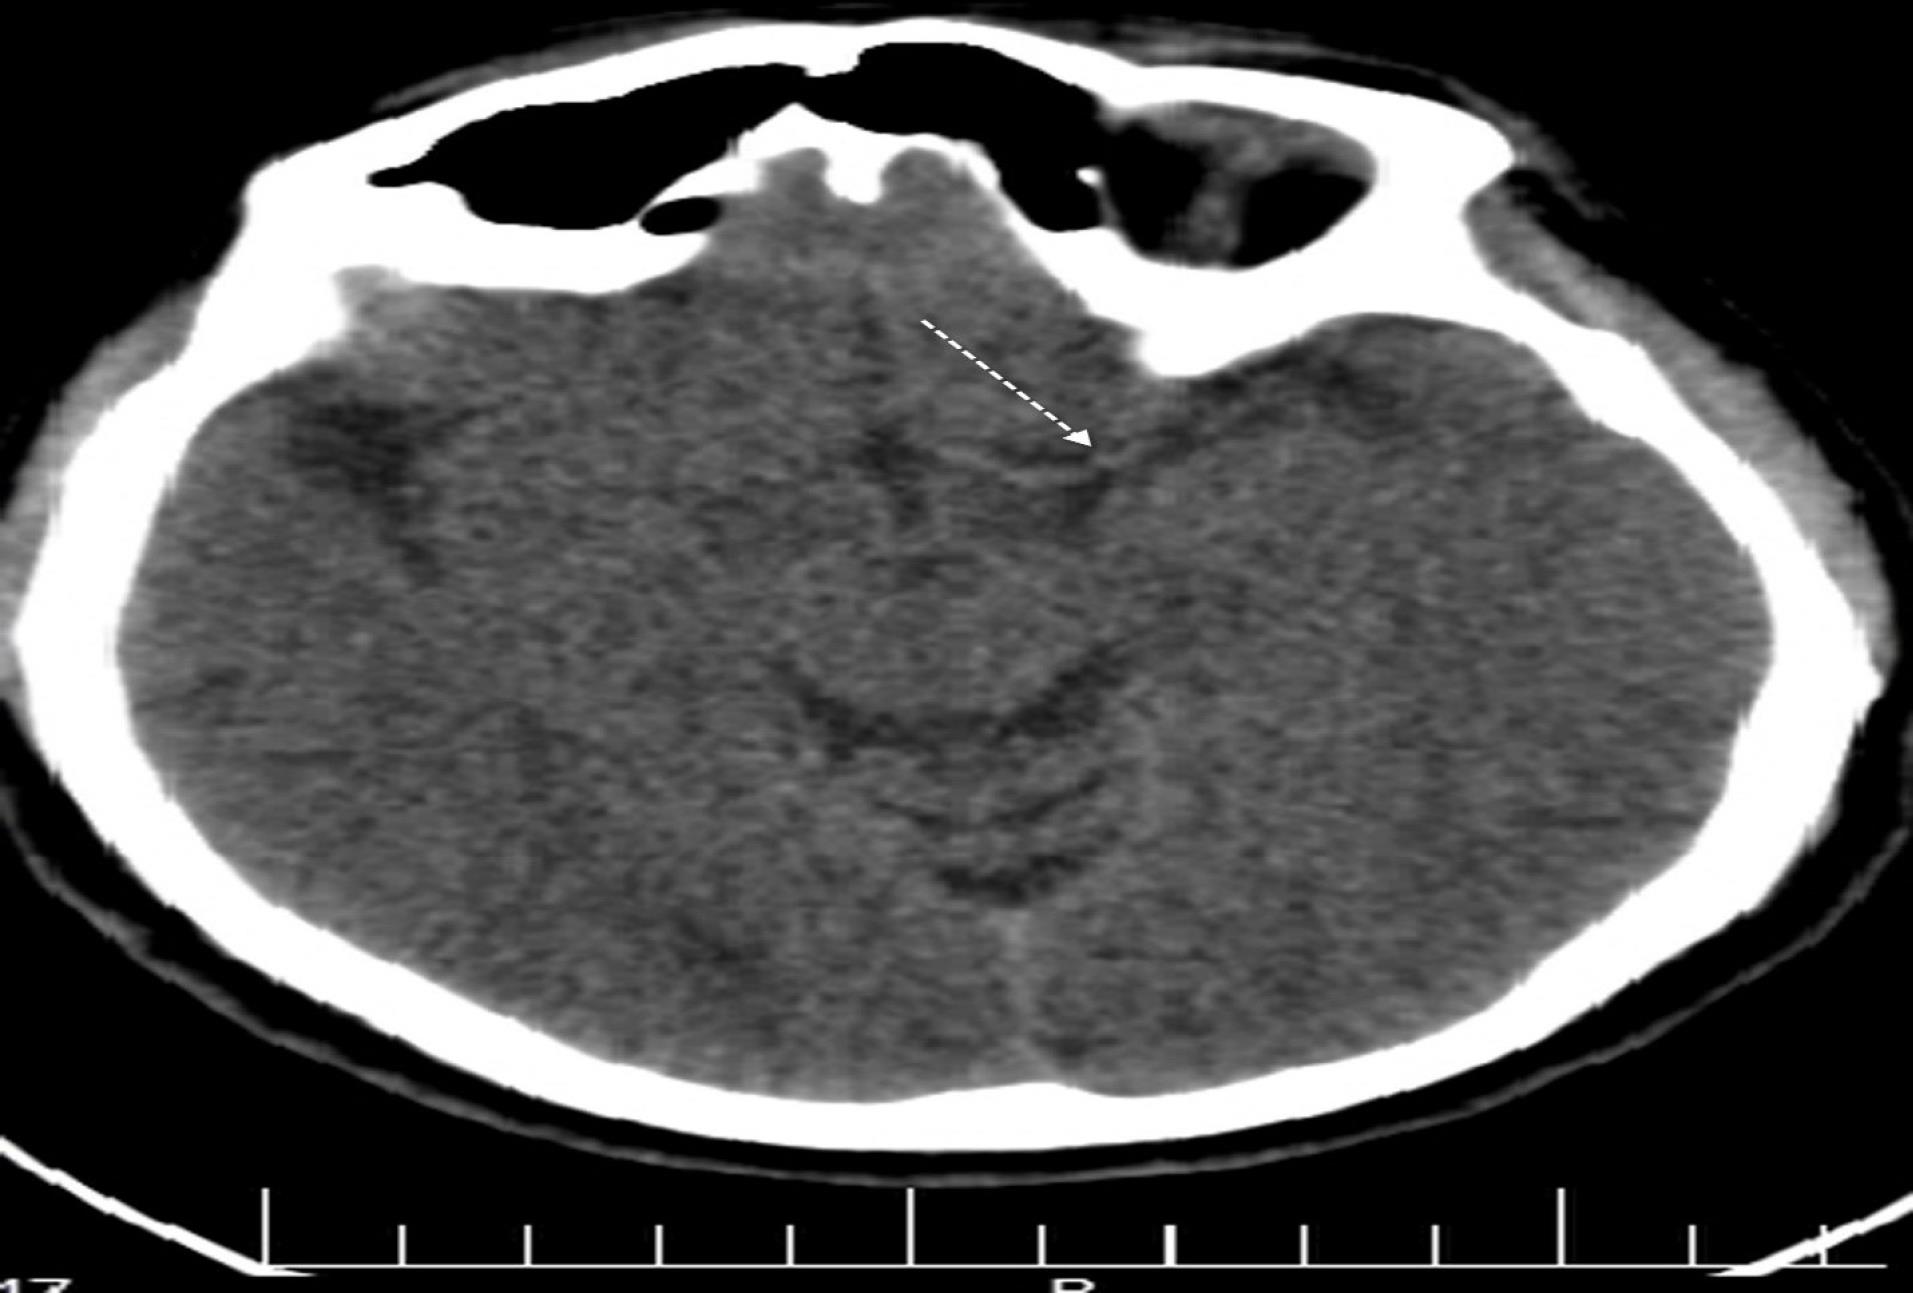

The patient was rehydrated with infusion of 1000 mL 0.9% sodium chloride (normal saline) within one hour, followed by maintenance infusion of 2500 mL over the next 24 hours. A single vial of tetanus toxoid was administered, and combination antibiotic therapy with ciprofloxacin and clindamycin was initiated. A non-contrast brain tomography scan performed 6 hours after admission revealed hyperattenuation of the MCA, suggestive of an occluding clot in the artery (Figure 3). Five vials of polyvalent antivenom were re-administered 12 hours later in accordance with guideline.4 Twenty-four hours following the snakebite (day 2), the patient regained consciousness and was extubated. Care was continued for the subsequent 24 hours. By day 3, neurological examination yielded unremarkable results. Muscle strength in the upper and lower extremities measured at 5/5. Repeat computed tomography was not performed as the patient’s recovery was progressing rapidly. On day 4, the patient was ambulating without assistance. No signs of clumsiness or loss of balance were observed. He was discharged home on day 6 with normal laboratory results and in good general condition.

Figure 3.

Non-contrast Computed Tomography Scan of the Brain Showing Left Dense Middle Cerebral Artery Sign (Also Known as Gács sign) in Patient with Vipera lebetina Envenoming